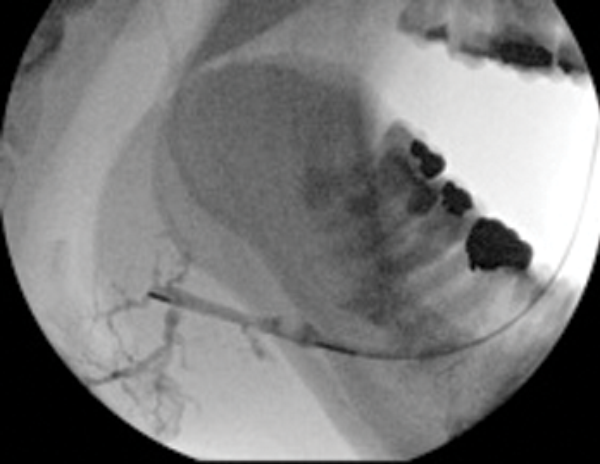

Figure 3: (A) The preoperative sialogram identifying a stone in the middle third of the submandibular duct.

Figure 3: (B) The insertion of a Dormia basket (closed).